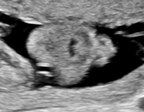

| Abdominal | Brain | Femur | Lips | |

| Device A | ![]() |

![]() |

| Device B | ![]() |

| Histogram | ![]() |

We demonstrate the practical applicability of our method on a challenging medical application, the classification of standardized fetal ultrasound (US) views during prenatal screening. In many countries, US imaging is clinical routine for prenatal health care. The classification of standardized views is important for a consistent, cross-institutional identification of possible abnormalities [47]. Early detection of pathological development can inform following treatment and delivery options [55, 25]. DNNs have shown promising performance to support this task [2]. However, ultrasound images are often hard to interpreted [40]. Anatomical structures have inconsistent appearance [2] and contain different orientations and shapes of anatomical landmarks [1]. Labeled training data is often insufficient as annotating medical images requires significant expertise and is prohibitively expensive in both time and labor. Manifestation of acoustic shadows [17, 44] as shown in Fig. 2(a) as well as different imaging devices as shown in Fig. 2(b) can lead to a domain shift problem for vanilla DNN classifiers. Exploring domain adaptation in fetal US enables DNN classifiers to be effectively utilized on a wider range, which supports identification of abnormalities from varying data sources. This can benefit prenatal healthcare.

We evaluate the proposed method on two fetal US standard plane classification tasks, where the domain shifts are respectively caused by shadow artifacts (Fig. 2(a)) and different image acquisition devices (Fig. 2(b)). For both tasks, images from source and target domains are unpaired and collected independently. We show the key results in the main paper and detailed implementation, network architectures as well as more results in the supplemental Appendix.

IV-D Experiments on cross-device fetal US

The previous experiment on fetal US images is supported by data restricted to one US imaging device. Here, we evaluate MIDNet for a standard plane classification task on data from different imaging devices (different device domains). Device A is “GE Voluson E8” which is the same device in Sec. IV-C, which acquired 2D fetal US images. Device B is “Philips EPIQ V7 G” which acquired another images sampled from about 500 2D US examinations with gestational ages between 20-32 weeks (see Fig. 2 (b)). In this experiment, we use four different anatomical standard plane locations with sufficient images in both domains, including Abdominal, Brain, Femur and Lips, which are selected by an 10-year-experienced sonographer. In this experiment, the source domain is set as device A while the target domain is device B. Training data consists of all four standard planes from the source domain as well as Abdominal and Brain from the target domain. We aim to separate anatomical features (categorical features) and imaging device features (domain features) to obtain generalized anatomical features for achieving high performance of standard plane classification on (Femur and Lips). Here, contains Abdominal, Brain, Femur and Lips from the source domain and contains Abdominal and Brain from the target domain. Hyper-parameters to in Eq. 11 are for the proposed MIDNet model and is additionally for MIDNet+.